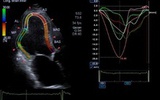

Nat Rev:影像学检测新法可追踪心脏衰竭病情

香港大学玛丽医院的研究人员概况了一种新颖的影像学检查方法:3D室臂运动追踪技术在心脏衰竭疾病中的应用,指出这种新方法未来将在这一领域发挥越来越重要的作用,相关成果公布在Nature Reviews Cardiology杂志上。